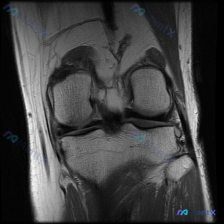

今天遇到一个挺有代表性的病例,主诉提示膝关节半月板异常,只提供了单张膝盖MRI冠状位T1加权像,整理一下分析思路跟大家分享。 一、病例核心信息 核心问题:患者主诉提示半月板异常,仅提供单一层面冠状位T1加权MRI读片 影像观察结果: 1. 骨骼:股骨远端、胫骨近端骨皮质完整连续,骨髓腔T1信号为均匀...

看到这张膝关节MRI的读片请求,目标是找半月板异常,但整理完全片发现这个病例的陷阱挺典型,分享出来给大家参考。 一、病例影像基本信息 这是一张膝关节冠状位T1加权磁共振图像,只有单一层面单序列,我们先按结构捋一遍所见: 1. 骨骼结构:股骨远端、胫骨近端骨皮质连续,没有明显骨折线;但整个骨髓腔在T1...

看到这个病例挺有代表性的:临床怀疑半月板异常,但提供的只有单张膝关节MRI冠状位T1加权序列,读片下来居然没发现明确异常,整理一下我的分析思路给大家参考。 先整理病例影像核心信息 这是膝关节MRI冠状位T1加权序列,我们先明确序列特点:T1加权主要看解剖结构,脂肪/骨髓是高/中高信号,液体、皮质骨、...

拿到这份病例和影像,先整理一下所有信息,再梳理思路: 一、核心临床问题 本次提出的核心疑问是:判断是否存在半月板异常 二、现有影像学发现(膝关节MRI T2序列冠状位单层面) 我先把所有客观发现整理出来: 1. 骨骼与关节软骨:股骨远端、胫骨近端骨皮质连续,无骨折;骨髓信号均匀,无明显水肿/硬化;关...

病例读片分享:临床怀疑半月板异常,单层面MRI怎么看? 今天整理了一份膝关节MRI读片病例,核心问题是临床怀疑半月板异常,但我们拿到的只有一份单冠状位的脂肪抑制序列图像,分享一下我的分析思路。 一、影像基本信息 这是一张膝关节MRI的冠状位脂肪抑制(PD-FS或T2-FS)扫描图像,这类序列对水/液...

看到一份膝关节MRI的影像资料,问题是观察半月板异常,整理一下完整分析思路分享给大家。 病例基本影像信息 这是一份膝关节冠状位T1加权MRI的单影像分析,核心异常聚焦在半月板: 1. 骨骼结构:股骨远端、胫骨近端骨质信号均匀,无骨髓水肿、骨质破坏,皮质连续完整 2. 关节软骨:关节面软骨形态规整,无...

看到一个有意思的影像讨论病例,整理一下资料和思路分享给大家。 病例背景 提问:单张膝关节冠状位MRI图像,问题是图像中可见的异常是什么,提示半月板异常。 影像初步分析 先确认这张影像的基本信息:这是膝关节冠状位MRI,对比良好,骨髓信号正常,可以看到股骨远端、胫骨近端、内外侧关节间隙、半月板和侧副韧...